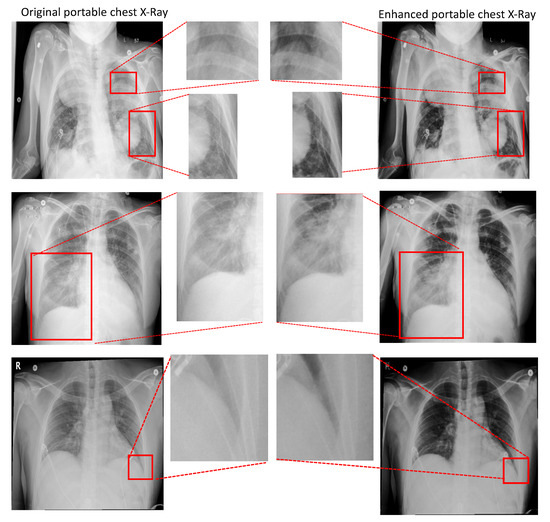

4.3.2. Portable Radiographs Quality Enhancement

- Thirdly, we propose a new PairFlow approach, an end-to-end invertible transfer of a deep learning method, to enhance the degraded CXRs from the portable machine. High-quality knowledge is then transferred to a degraded domain to increase the portable CXRs quality.

| Por.CXR vs. Con.CXR | Enh.CXR vs. Con.CXR | Por.CXR vs. Con.CXR | Enh.CXR vs. Con.CXR | |

| 28.019/0.245 | 30.273/1.798 | 0.936/0.018 | 0.960/0.011 | |

| 28.003/0.236 | 30.437/1.707 | 0.748/0.047 | 0.787/0.045 | |

| 29.009/0.229 | 30.474/1.724 | 0.919/0.021 | 0.955/0.013 | |

| 28.006/0.227 | 30.522/1.662 | 0.729/0.050 | 0.780/0.047 | |

| 28.011/0.205 | 30.407/1.670 | 0.873/0.035 | 0.920/0.021 | |

| 28.009/0.198 | 30.498/1.629 | 0.839/0.044 | 0.910/0.026 | |